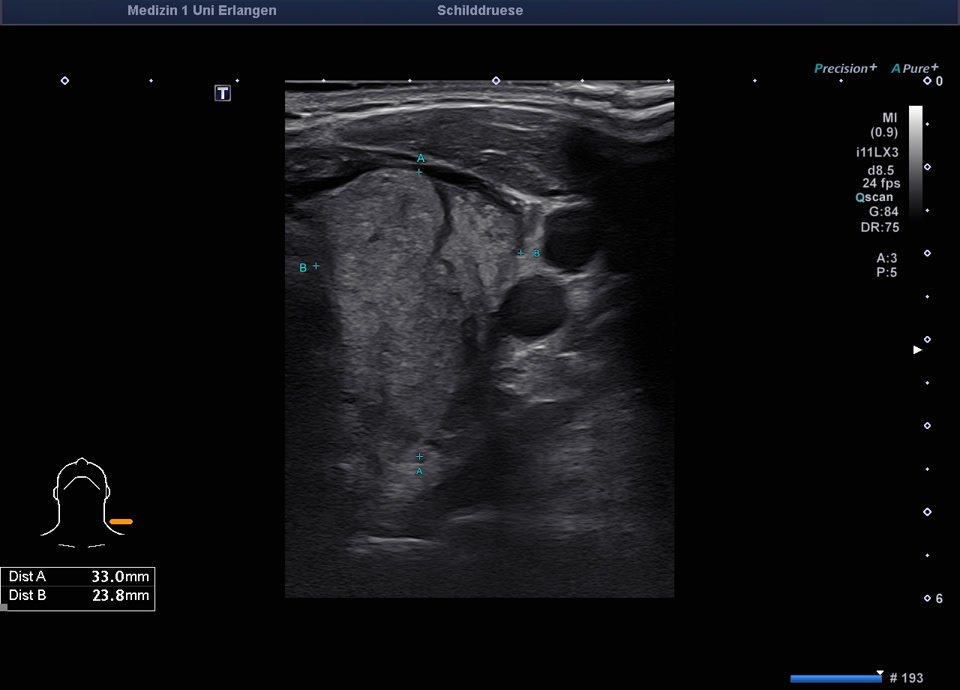

45-year-old male presented patient with persistent sore throat and general symptoms following an EBV-infection. An external diagnosis of post-infectious de Quervain’s thyroiditis had already been made, and a two-week course of corticosteroid therapy was administered. Initial clinical improvement with reduced throat pain was noted under treatment, but symptoms reoccurred after discontinuation of corticosteroids. Laboratory findings revealed leukocytosis of 12,000/µl and CRP of 113 mg/l. Sonographically, a bilaterally enlarged thyroid gland with diffusely hypoechoic areas and inhomogeneous parenchyma was observed. Combined with the patient history, this was characteristic of a subacute thyroiditis with relapse after short-term corticosteroid therapy. Prolonged corticosteroid therapy with slow tapering was performed. Under this regimen, marked clinical improvement occurred within weeks; follow-up ultrasound four months later showed a normal-sized thyroid with only mildly inhomogeneous parenchyma, consistent with resolving thyroiditis.